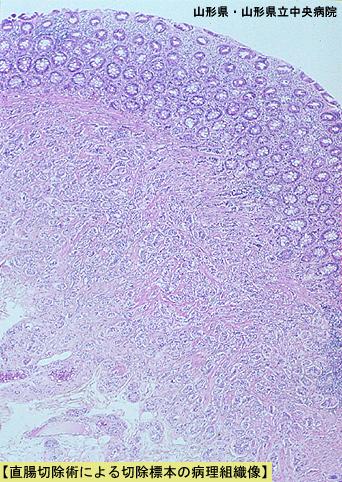

림프절 전이를 동반한 10mm 이하의 다발성 직장 카시노이드 (증례제시:야마가타현, 야마가타현립 중앙병원, Dr.이케다)

마이크로